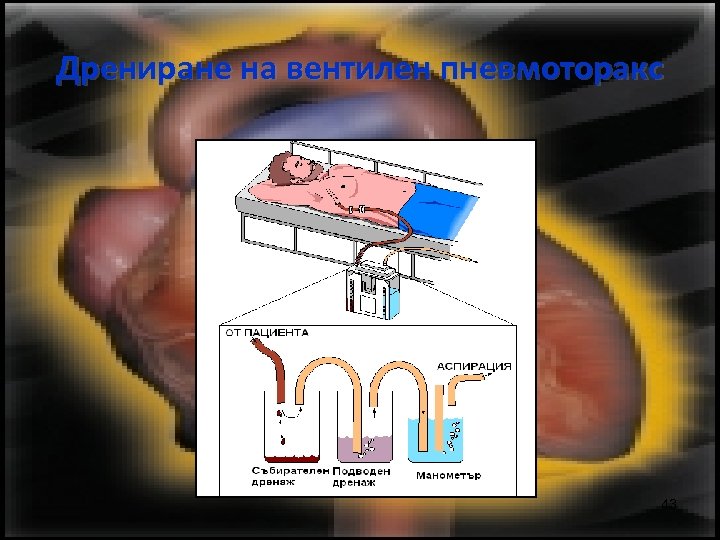

Дрениране на вентилен пневмоторакс 43